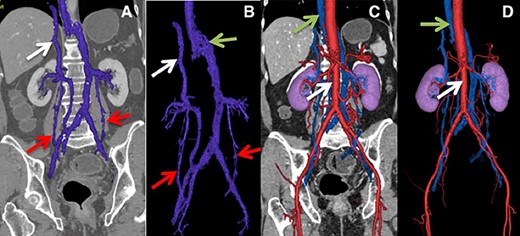

A 14-year-old male, without relevant history, consulted the urologist for enuresis and was diagnosed with the right varicocele. CT angiography was performed, showing an IVC anomaly, with partial hypoplasia of the upper segment, persistence of the left SVC to which the left and right renal veins drain, the left renal vein with a retro-aortic segment showing signs of aorto-vertebral impingement, a right dilated and tortuous testicular vein ending in the right renal vein and continuation of the azygos in the visualized thoracic segment. (Fig. 2).

(A and B) Lower arrow shows testicular vein, upper arrow shows hypoplastic suprahepatic segment of the IVC. (C) Lower arrow shows aorta, upper arrow indicates azygos vein. (D) Lower arrow shows aorta, middle arrow shows retro-aortic right renal vein, upper arrow shows azygos vein.